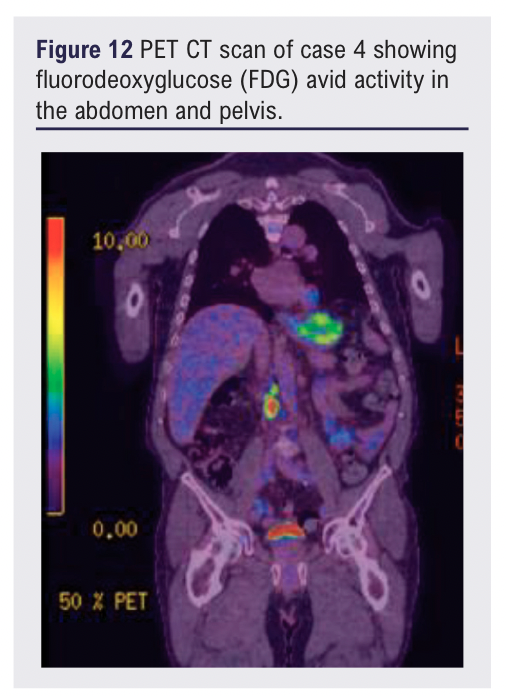

At review, in addition to the left groin mass, two lateral thigh lesions were identified. The patient was otherwise clinically well with no systemic symptoms. Subsequent MRI confirmed an 11 cm subcutaneous mass encasing the great saphenous vein without muscular invasion. A PET-CT scan showed FDG avid activity in the thigh lesions as well as the abdomen and pelvis (see Figures 11 and 12).

The role of advanced imaging modalities such as MRI and PET-CT is increasingly important when lesions exhibit atypical characteristics. PET imaging is particularly valuable in the assessment of marginal zone lymphoma and has been shown to correlate with disease burden and staging, especially in relapsed or extranodal presentations.10,11 This should be considered early in patient pathways where there is a history of adulthood haematological malignancy.